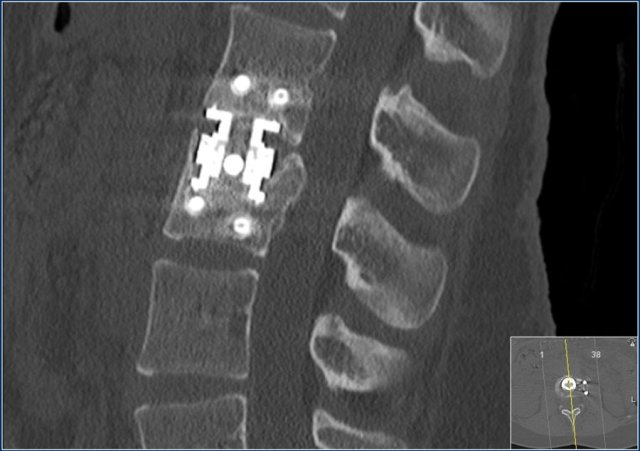

This is an interesting case since non-surgical management was initially attempted in this patient.

However when we classify according to the TLICS-score, we give 4 points for the morphology and 3 points for the PLC.

Assuming the neurological exam was normal, this patient would still get 7 points.

Unfortunately, but not unexpectedly, conservative management failed with near-dislocation.

Finally a posterior spondylodesis was performed.